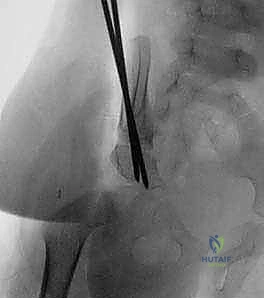

- التثبيت الداخلي: لتأمين العظام في وضعها الجديد والمستقر، يستخدم الدكتور هطيف أسياخاً معدنية رفيعة وقوية تُعرف بأسياخ كيرشنر (K-wires). يتم إدخال هذه الأسياخ عبر العظام لتثبيت الطعم العظمي والحوض معاً حتى يلتئم العظم (تستغرق عملية التئام العظم عادة حوالي 6 أسابيع).

- الإغلاق والتجبيس: بعد التأكد من استقرار المفصل باستخدام الأشعة السينية داخل غرفة العمليات (Intraoperative Fluoroscopy)، يتم خياطة الجرح تجميلياً. وأخيراً، يتم وضع الطفل في جبس خاص يسمى "بنطلون الجبس" (Spica Cast)، والذي يغطي نصف الجسم السفلي (من الخصر وحتى الكاحل في الساق المصابة، وإلى الركبة في الساق السليمة) لضمان عدم تحرك المفصل أثناء فترة الشفاء.